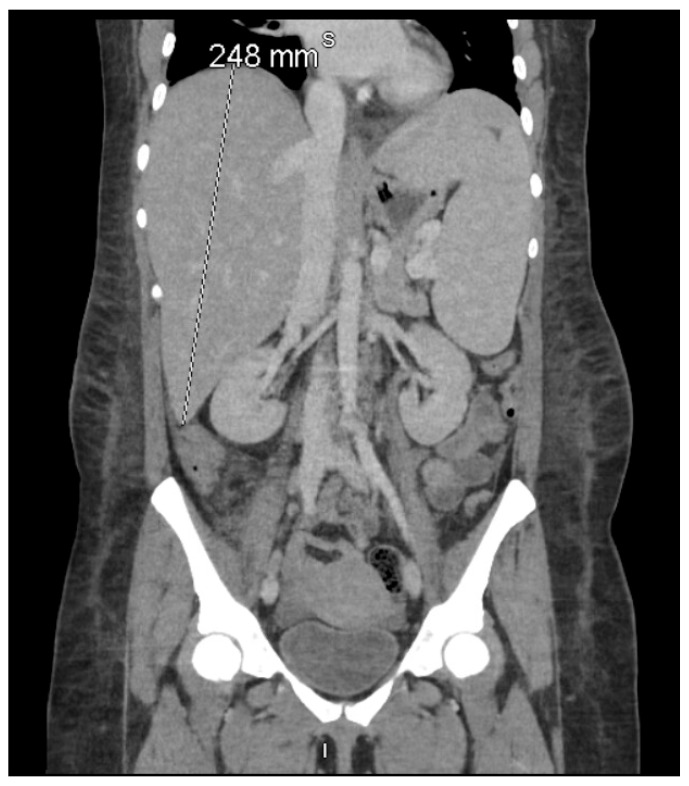

背景和临床意义:噬血细胞淋巴组织细胞增多症(HLH)和自身免疫性溶血性贫血(AIHA)都是危及生命的血液学综合征,除恶性肿瘤外很少同时出现。晚期获得性免疫缺陷综合征(艾滋病)造成了严重的免疫失调和过度炎症的环境,使患者容易出现这些疾病的非典型重叠。病例介绍:一名30岁妇女,艾滋病控制不佳,表现为黄疸、发热和疲劳三周。初步化验显示全血细胞减少症、高胆红素血症和铁蛋白水平升高。直接抗球蛋白试验证实温暖AIHA (IgG+/C3d+)伴有短暂冷凝集素。尽管静脉注射免疫球蛋白(IVIG)、美罗华(rituximab)和输血,她仍出现肝脾肿大、极端高铁蛋白血症和sIL-2R bbb10万pg/mL,符合HLH-2004标准。骨髓活检排除恶性肿瘤;进一步检查发现eb病毒(EBV)病毒血症和巨细胞病毒(CMV)再激活。地塞米松加减少剂量的乙泊苷可短暂降低可溶性白细胞介素-2受体(sIL-2R),但可引起深度全血细胞减少症、巨细胞病毒/副流感肺炎引起的急性呼吸窘迫综合征(ARDS)、双侧深静脉血栓形成(DVT)和st段抬高型心肌梗死(STEMI)。她最终死于抗凝后失血性休克,尽管最大的支持措施。结论:该病例强调了艾滋病患者中hhl - aiha重叠的诊断挑战,其中细胞减少症和高铁蛋白血症掩盖了潜在的细胞因子风暴。发病机制可能涉及IL-6/IFN-γ过量产生、细胞毒性t细胞功能受损和分子模仿。虽然依托泊苷仍然是HLH治疗的基石,但其骨髓毒性在这种免疫功能低下的宿主中被证明是灾难性的,这突出了迫切需要细胞因子靶向药物来降低治疗相关的死亡率。

Background and Clinical Significance: Hemophagocytic lymphohistiocytosis (HLH) and autoimmune hemolytic anemia (AIHA) are both life-threatening hematologic syndromes that rarely present together outside of malignancy. Advanced acquired immunodeficiency syndrome (AIDS) creates a milieu of profound immune dysregulation and hyperinflammation, predisposing patients to atypical overlaps of these disorders. Case Presentation: A 30-year-old woman with poorly controlled AIDS presented with three weeks of jaundice, fever, and fatigue. Initial labs revealed pancytopenia, hyperbilirubinemia, and elevated ferritin level. Direct anti-globulin testing confirmed warm AIHA (IgG+/C3d+) with transient cold agglutinins. Despite intravenous immunoglobulin (IVIG), rituximab, and transfusions, she developed hepatosplenomegaly, extreme hyperferritinemia, and sIL-2R > 10,000 pg/mL, meeting HLH-2004 criteria. Bone marrow biopsy excluded malignancy; further work-up revealed Epstein-Barr virus (EBV) viremia and cytomegalovirus (CMV) reactivation. Dexamethasone plus reduced-dose etoposide transiently reduced soluble interleukin-2 receptor (sIL-2R) but precipitated profound pancytopenia, Acute respiratory distress syndrome (ARDS) from CMV/parainfluenza pneumonia, bilateral deep vein thrombosis (DVT), and an ST-elevation myocardial infarction (STEMI). She ultimately died of hemorrhagic shock after anticoagulation despite maximal supportive measures. Conclusions: This case underscores the diagnostic challenges of HLH-AIHA overlap in AIDS, where cytopenias and hyperferritinemia mask the underlying cytokine storm. Pathogenesis likely involved IL-6/IFN-γ overproduction, impaired cytotoxic T-cell function, and molecular mimicry. While etoposide remains a cornerstone of HLH therapy, its myelotoxicity proved catastrophic in this immunocompromised host, highlighting the urgent need for cytokine-targeted agents to mitigate treatment-related mortality.